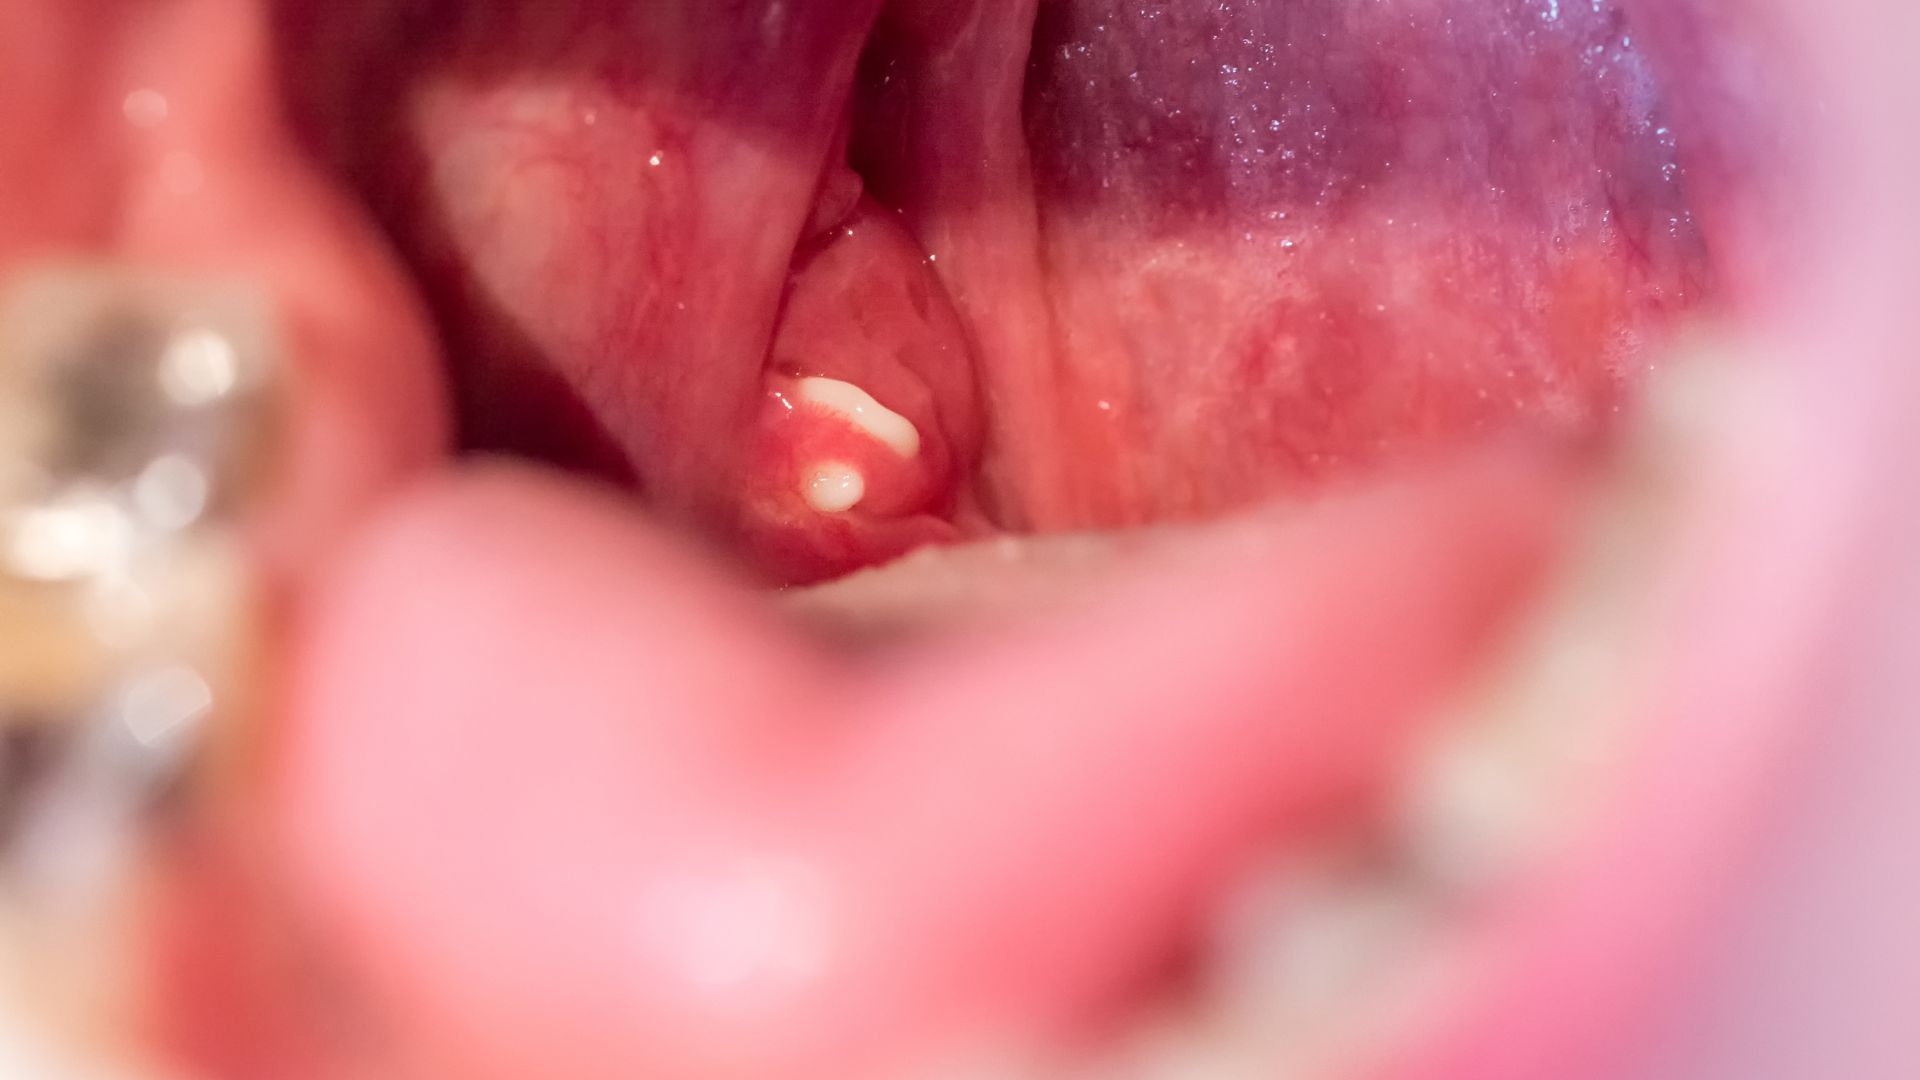

Viêm amidan hốc mủ là tình trạng amidan bị viêm mạn tính, trong các hốc xuất hiện chấm hoặc khối mủ trắng vàng. Đây là giai đoạn tiến triển của viêm amidan lâu ngày, khi vi khuẩn và tế bào chết tích tụ lại trong hốc amidan tạo thành “hạt mủ” có mùi khó chịu.

- Đôi khi khạc ra cục mủ nhỏ có mùi hôi đặc trưng.